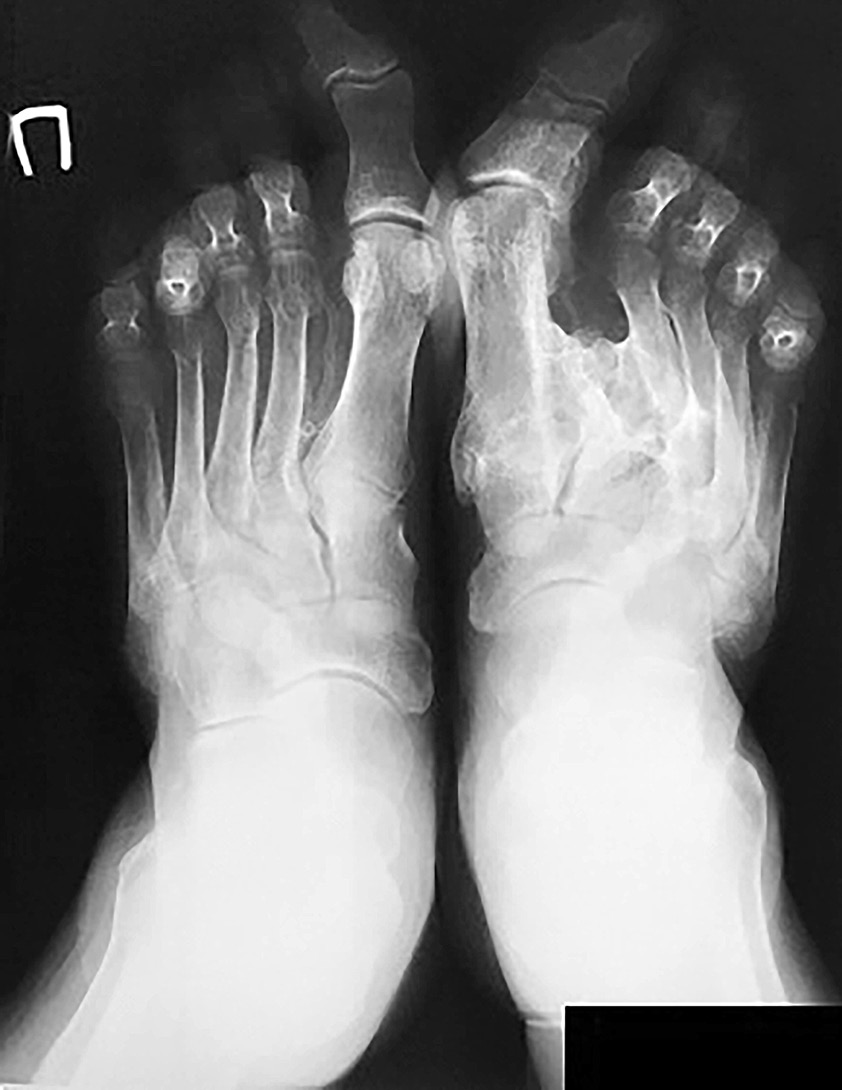

Рис. 7. Рентгенограмма обеих стоп при поступлении, 2018 г.

На рентгенограмме (рис. 7) отмечены признаки диффузного остеопороза, наличие участков фиброзно-кистозной перестройки в дистальных эпиметафизах большеберцовой и малоберцовой кости, таранных костях. Левая стопа деформирована за счет консолидации со смещением отломков оснований 1–4-й плюсневых костей с массивными периоссальными наслоениями и нарушением конфигурации в суставе Лисфранка. Отмечаются подвывихи в межфаланговых суставах 2-го, 4-го, 5-го пальцев, молоткообразная деформация плюсневых и фаланговых косточек, деформирующий артроз в плюснефаланговых и межфаланговых суставах; признаки диффузного остеопороза, фиброзно-кистозной перестройки эпиметафизов фаланг и костей плюсны и предплюсны. На рентгенограмме правой стопы в прямой проекции отмечается варусная деформация, hallux valgus 1-го пальца с подвывихом в межфаланговом суставе, пальцы стопы клювовидно искривлены в подошвенную сторону, с акцентом на 4-й палец, межплюсневые промежутки расширены. Фаланги пальцев и плюсневые кости молоткообразно деформированы, с фиброзно-кистозной перестройкой эпиметафизов. На рентгенограмме левого и правого коленного сустава – остеопороз, остеоартроз справа с посттравматической деформацией медиального мыщелка правой большеберцовой кости с перестройкой межмыщелкового ареолярного поля и девиацией межмыщелковых возвышений правой большеберцовой кости кнаружи. Консолидированный перелом диафиза правой малоберцовой кости.